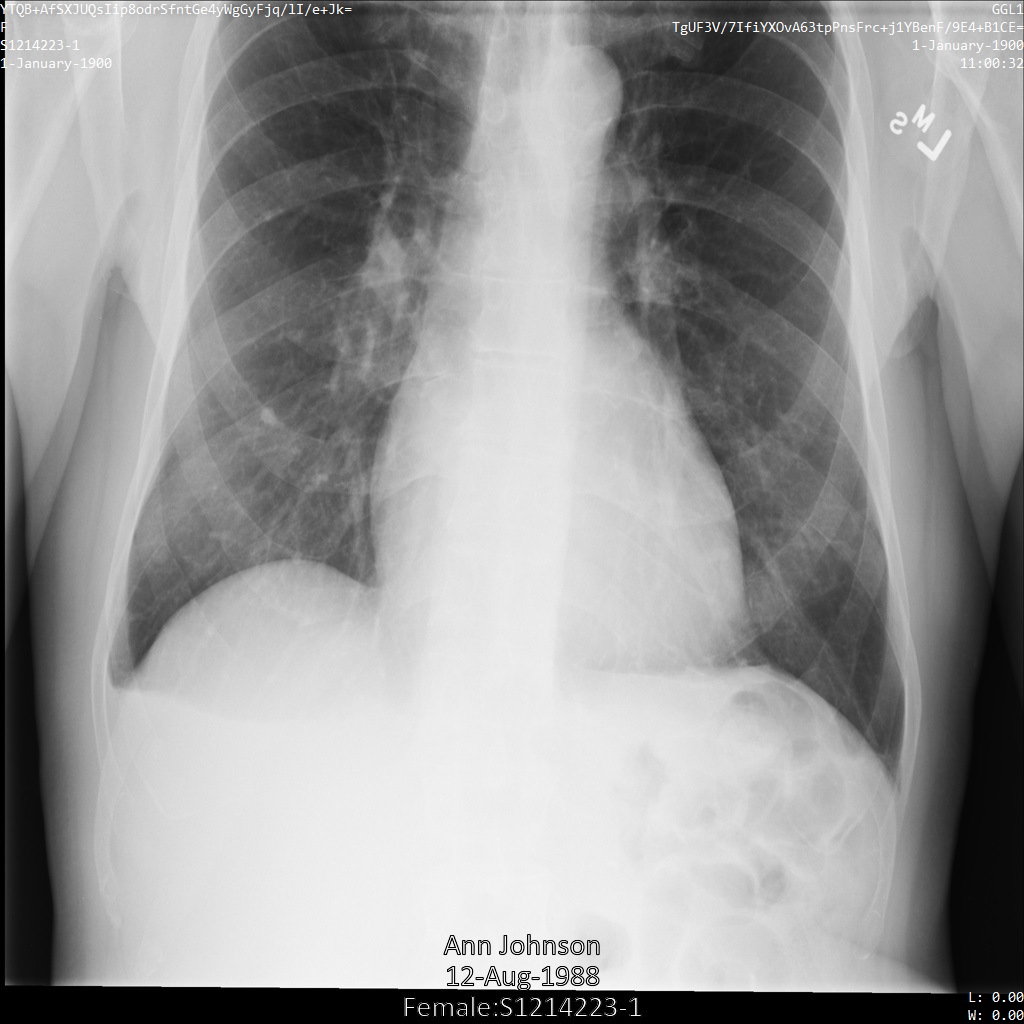

Después de enviar la imagen a la API de Cloud Healthcare, la imagen aparece de la siguiente manera. De las etiquetas proporcionadas en la removelist, solo se quita PatientBirthDate en la imagen, ya que es la única etiqueta de la lista de eliminación que corresponde a los metadatos visibles en la imagen.

Si bien PatientBirthDate en la esquina superior de la imagen se ocultó de acuerdo con la configuración de la removelist, la PHI de efecto quemado que se encuentra en la parte inferior de la imagen permanece. Para quitar también el texto quemado, consulta Cómo ocultar el texto quemado de las imágenes.